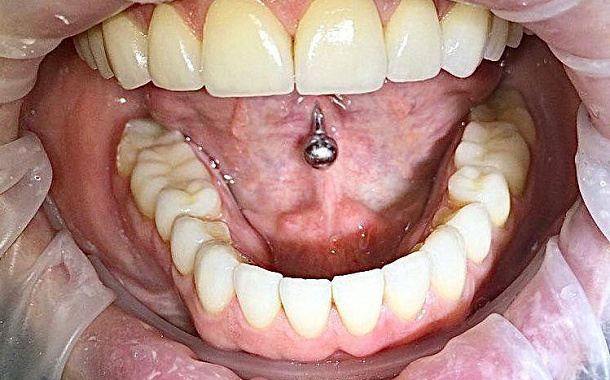

Большинство пациентов воспринимают керамические виниры как зубные накладки, с помощью которых можно создать красивую улыбку. Да, она всегда будет идеальной и обворожительной, ведь виниры годами сохраняют оттенок и естественный блеск эмали. Но это еще не все их преимущества.

С точки зрения стоматологии, реставрация зубов винирами — это прежде всего восстановление правильного функционирования зубочелюстной системы. Когда все ее составляющие работают правильно, тогда и улыбка пациента ослепительная, и черты лица гармоничные.